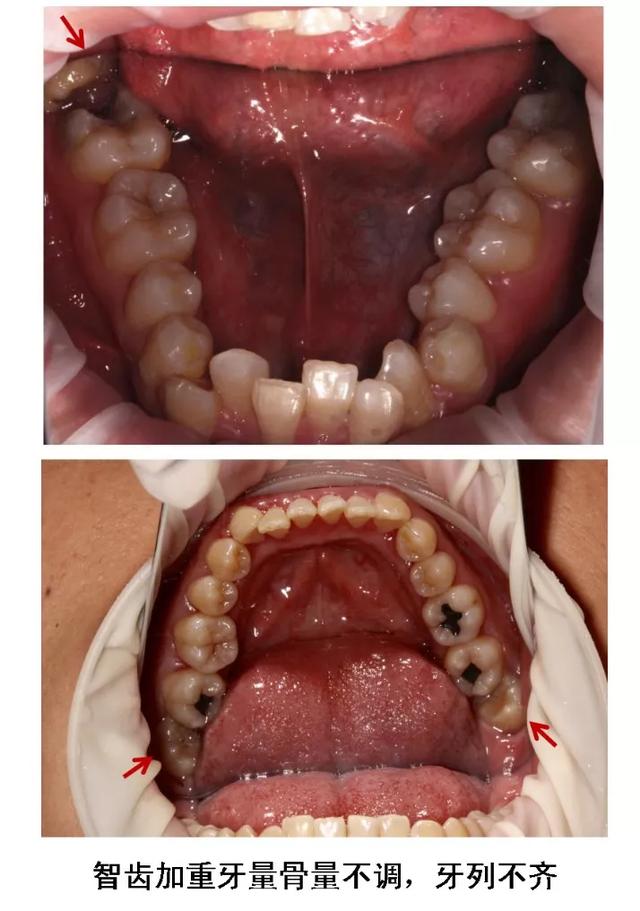

6、牙齿需要矫正,以及在12-16岁做过矫正的小朋友,需要根据正畸医生的建议,及时拔除智齿,以获得完美的牙列和脸型!